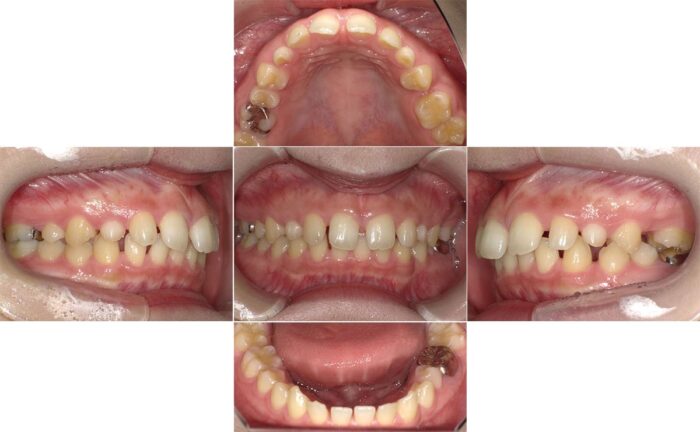

前歯のすきっ歯の改善と目立たない矯正装置を希望され、マウスピース矯正装置(インビザライン)で治療を始めました。ところが、治療開始5ヶ月を過ぎた頃から、大学生になり環境の変化で、通院間隔が9ヶ月間も空いてしまいました。

そのため、マウスピースが合わなくなってしまい、ワイヤー矯正へ変更の提案をしましたが、目立つ装置は避けたいということで奥歯だけワイヤー矯正をつけて補正することになりました。

7ヶ月間、装置を併用した治療を行い、その後マウスピースのみで細かい微調整とかみ合わせの調整を行いました。通院間隔が空いてしまったこと以外は問題なく治療が進み、すきっ歯が改善されました。

- 主訴:すきっ歯が気になる

- 診断名:空隙歯列・過蓋咬合

- 初診時年齢:17歳・女性

- 使用装置:マウスピース矯正装置(インビザライン)・表側ワイヤー矯正

- 抜歯部位:上顎左右犬歯・上顎左側第二小臼歯(欠損)、上顎右側乳犬歯

- 治療期間:3年6ヵ月

- 費用:865,000円(税込951,500円)

- リスクと副作用:痛み、歯根吸収、歯肉退縮、むし歯、後戻り